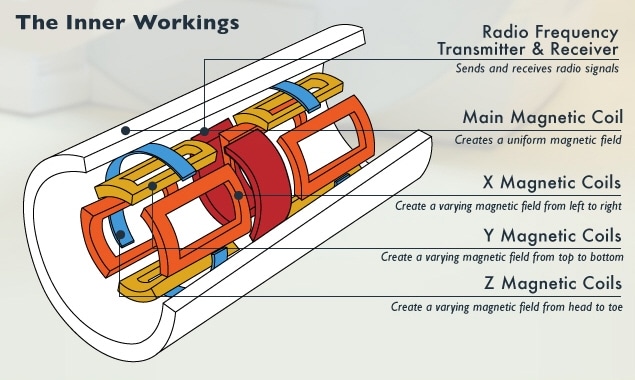

Magnetic resonance imaging (MRI) is a completely different way of viewing inside parts of the body. It relies on the way hydrogen nuclei respond to magnetic fields. Functional MRI (fMRI) is a specialized version used in the brain, tracking oxygen instead to image blood flow based on oxygenation levels.

This process works by placing the body in a strong static magnetic field so that all the nuclei are oriented in the same direction. A varying field is then created to perturb the atoms locally; this re-orients them from their starting position. When that varying field is removed, the cell processes back to the static position. Different cells relax at different rates, ranging from tens of milliseconds to over one second, and the decay signals given off as the cells move back – in the 1 to 300 MHz range – create the image (see Figure 5). It is these differences in the relaxation timing that allow the system to discriminate different kinds of tissues.

A superconducting magnet, tweaked by “shim” coils, establishes the static field. Localization is handled through gradient coils that establish fields in the x, y, and z directions that vary according to position (see Figure 6). The coils for stimulating the nuclei are also used as (or placed together with) the coils that detect the response. Traditionally the excitation happens at frequencies higher than what can be handled in the front end, so the transmitted signal is up-converted to the coils and the received signal is down-converted for processing. As component performance improves, processing will be possible in the working frequency without conversion. Figure 7 shows the block diagram for an MRI system.

Figure 6: MRI transmitter, receiver, and coils.